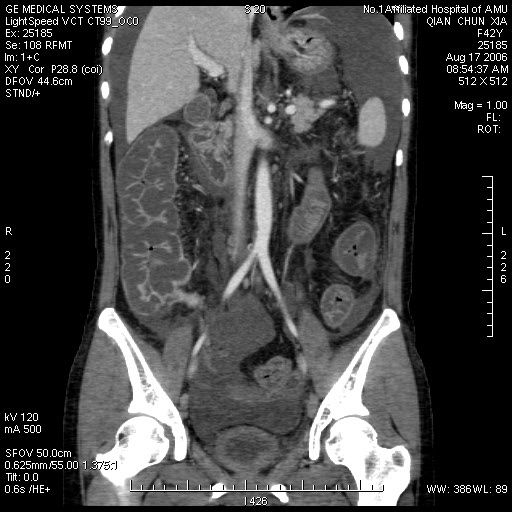

增强

真是少见!至少本人从未见过!整个消化道除了胃壁以外整套小肠及结肠肠壁均不同程度增厚水肿,肠壁间未见积气,亦未见明显的血运障碍(肠细膜上动静脉均显示很好)。盆腹腔积液。

真是少见!至少本人从未见过!整个消化道除了胃壁以外整套小肠及结肠肠壁均不同程度增厚水肿,增强明显分层[粘膜层及浆膜层明显强化,粘膜下层强化轻]。结合病史考虑肠道缺血改变[病因待查--血管炎,结缔组织疾病等]

肠管全程水肿,向心性狭窄,冠状面重建显示门脉好象相对粗一些,增强扫描没有上传静脉期图象,不知道腔静脉肝段和肝静脉是否正常?是否有静脉回流异常??

我们仔细看了三期增强的动静脉血管,未看见血栓的形成,因为三期的片子太多有168张,无法全部上传,在动脉期及静脉期看到下腔静脉及门静脉内密度不均匀在平衡期均显示均匀,所以不考虑血栓形成引起的回流障碍.刚才老公在电脑边走过(他是外行),发表意见说这人是不是吃了什么东西引起肠子中毒.我想了一下似乎有道理,但是是什么东西会引起这样的改变,并且从病程上来看有一个多月的病史,又不是急性发作,网上高手们给予指点,如需要更多的另两期的图片,我将上传.

肠管壁增厚,以升结肠、横结肠明显,肠袋变浅,cta显示肠系膜上动、静脉显影清楚,管腔未见狭窄,同时大量腹水,考虑:肠麻痹水肿?食物中毒?

本例ct表现是肠道的整体性充血、水肿,以结肠特别是横结肠、升结肠、盲肠为显著,横结肠一眼粗略看过去,极似极度水肿之胰腺。回肠末段亦呈明显近似结肠改变,小肠则以充血为主,水肿相对轻微。诸段肠管无明显如溃疡、出血等局部损害,重度腹水。肝脏体积变小,肝裂增宽,以肝圆韧带为明显。肝脏各部比例尚正常,无局部外突或内凹,密度均匀一致。胆囊增大,所给图片及楼主已经仔细观察过,肝段下腔静脉肠系膜静脉均正常。

这个病例有脱发的病史,后转到风湿科,确诊为sle,经过一段时间的激素治疗,病情好转,以下是今日复查的ct